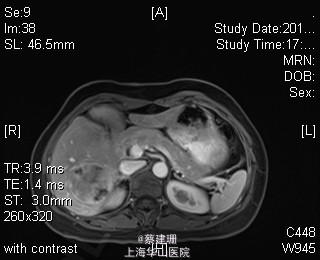

主诉:平滑肌肉瘤、肝转移癌术后,发现肝多发转移2月余。 现病史:患者3年前外院检查发现后腹膜肿瘤,外院行后腹膜肿瘤切除术后,术后病理为:平滑肌肉瘤,2013年12发现肝左叶转移癌,外院行肝左叶肿瘤切除术,术后病理为:梭行平滑肌肉瘤。2月余前患者复查发现肝脏多发转移,2015-4月肝脏MRI:肝脏多发转移。现患者无恶心、呕吐,无呕血、黑便,无皮肤巩膜黄染,无剧烈腹痛发作。现为进一步诊治收住入院。

查体:锁骨上淋巴结未扪及肿大;腹部平坦,可见陈旧性手术疤痕。未见肠型、胃型蠕动波,腹软,无压痛及反跳痛,无肌卫,肝脾肋下未及。Murphy’s 征(-),肝区叩击痛(-),肾区叩击痛(-);移动性浊音阴性。 辅查:2015-4月肝脏MRI:肝脏多发转移。

诊断 :1、多发肝转移癌 2、后腹膜平滑肌肉瘤术后 3、肝转移癌术后 处理:取右侧肋缘下切口,左侧延长,逐层切开进腹,探查腹腔:见上腹部粘连,仔细游离上腹部腹腔粘连,探查见无腹水,胃、肠、胰、脾及盆腔脏器未及异常,腹腔未见明显转移结节;肝脏无硬化。肝门淋巴结无肿大,门静脉主干无栓子。肿瘤多枚,最大两枚位于肝右叶VI段,肿瘤大小约7*6*5cm。V段肿瘤直径约5cm。左内叶肿瘤多枚,直径0.5-4cm,紧贴第一肝门。左外叶肿瘤多枚,直径1-3cm,肿块质韧,边界尚清,有包膜。术中诊断为转移性肝癌,决定行左半肝切除,肝右叶特殊肝段切除。